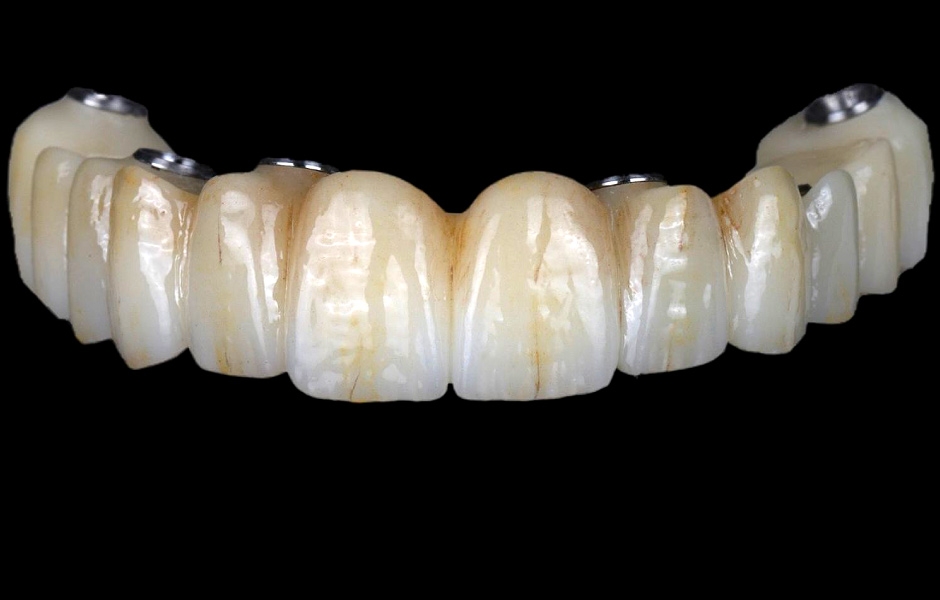

Použití plně navigovaného chirurgického protokolu ve spojení s kompletně digitálním postupem zhotovení protetiky umožnilo přesný návrh a následné vyfrézování provizorních náhrad z PMMA (obr. 34–35).

Pro kotvení definitivní náhrady byly použity abutmenty Variobase® for Bridge. Materiálem pro výrobu definitivní náhrady byl zvolen monolitický zirkon (obr. 49, 50).

Definitivní náhrada byla nasazena a ověřena z hlediska estetiky, okluze a funkce (obr. 51–55). Panoramatický kontrolní snímek potvrdil, že všechny parametry protetického ošetření odpovídají očekávaným hodnotám (obr. 56).

Obr. 34

Obr. 35

Obr. 49

Obr. 50